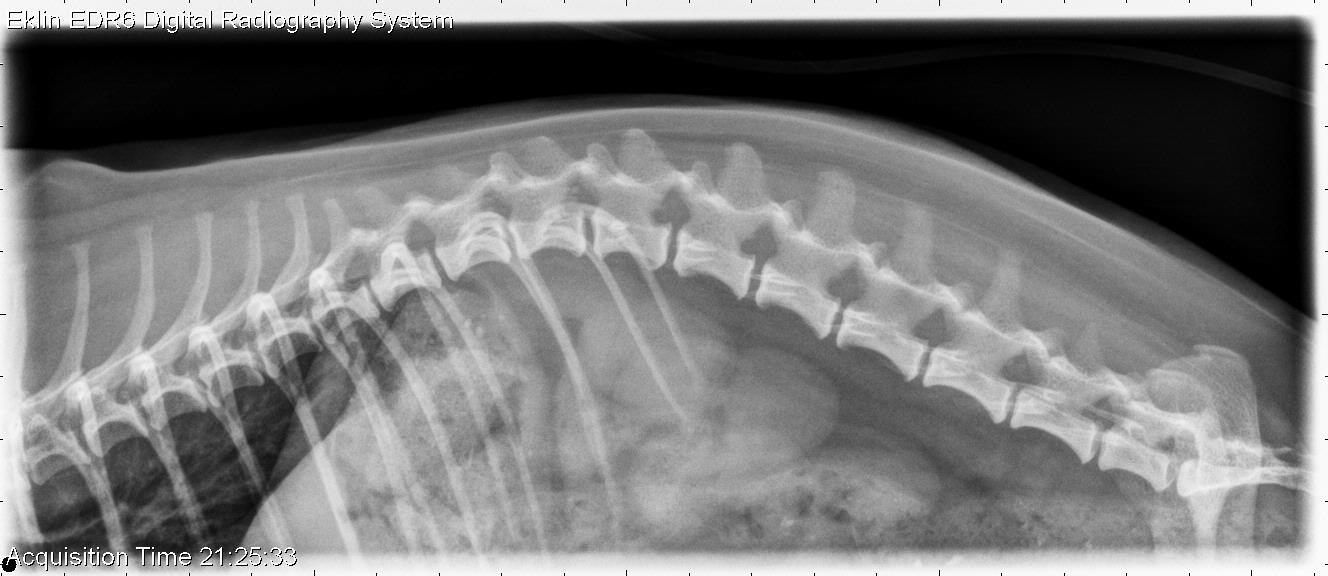

For our first case of November, we have a 4-year-old female neutered Yorkshire Terrier that was attacked by another dog. Now painful and tetraparetic. Spine radiographs are often our first imaging choice when evaluating animals for trauma. What are your findings?

Survey spine: On the lateral images of the cervical spine, there is a bone fragment dorsal to the C1 vertebra, with a rounded opacity cranial to it. These fragments are not well seen on the ventrodorsal projections. The remainder of the spine appears normal.

Myelogram: Contrast fills the subarachnoid space normally after an injection at L5-6. At C1-2, there is contrast leakage into the subcutaneous tissues dorsal to C1. There is splitting of the contrast column at C6-7 without attenuation of the dorsal contrast column.

• C1 fracture with possible luxation and dural tear

• Intervertebral disc herniation without spinal cord compression at C6-7

On CT images, the fracture of C1 and dural tear were confirmed. The dog recovered the ability to walk with conservative therapy and a neck brace. On these CT images, the fractures of C1 as well as contrast in the soft tissues can be seen.